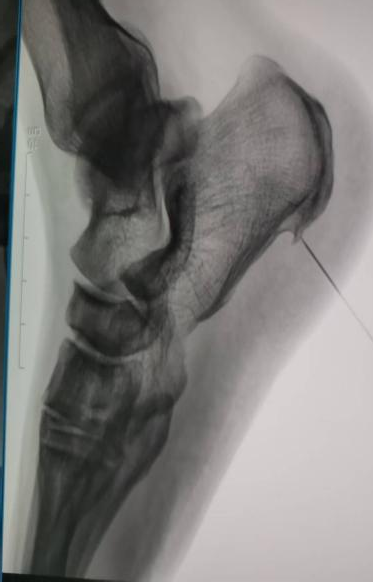

为了解决这个难题,我院足踝外科的医生们一直专研微创技术,还结合了国内外最先进的治疗经验,终于研究出了关节镜微创治疗的好方案。这个技术最大的好处就是伤口小、定位准、好得快:只需要在脚后跟骨头上开个约0.5厘米的小口,通过关节镜的高清镜头,直接找到病根。医生能清楚地看到发炎的部位,精准松解筋膜,清理掉发炎的坏组织;如果脚后跟还有骨刺,也能一起磨掉,从根儿上解决疼痛的问题。

这次做手术的患者,被足跟痛折磨了一年多,做了6个多月的保守治疗都没效果,正常生活都受大影响了。团队专门为他定制了手术方案,术前仔细做了检查、评估了身体状况,手术过程特别顺利。术后第二天,患者就在医生护士的指导下下床慢慢活动了,足跟的刺痛感明显减轻;伤口恢复得也特别好,没有渗血渗液,没多久就顺利出院了。复查的时候,患者的足底疼痛完全消失了,能正常走路、运动。